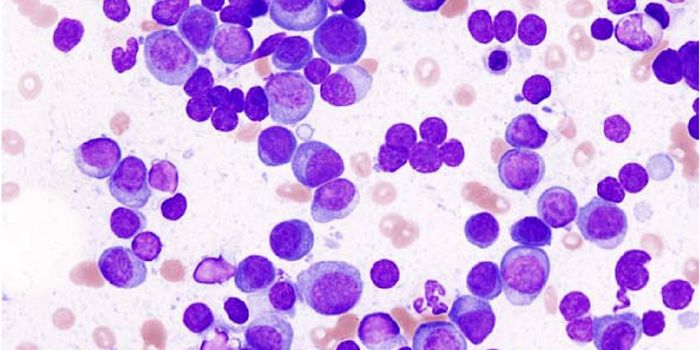

MAY 01, 2018CancerResearchers have developed a microfluidic device that can detect circulating plasma cells in whole blood; therefore, neg ...